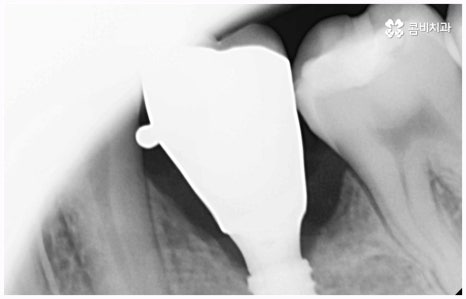

또한 임플란트 종류 중에 네비게이션임플란트라고 해서 3D-CT, 3D 컴퓨터 분석을 통하여 최적의 위치와 각도를 계산하여 정확하고 정밀하게 임플란트를 식립하는 방법이 있는데, 이와 같이 3D 모의 수술을 통해 제작된 가이드로 수술을 진행하게 되면 일반적인 경우 무절개, 필요한 경우 최소 절개를 하므로 통증이 적고 비교적 시술 시간이 짧아지며 상대적으로 출혈, 감염 등의 위험성을 줄일 수 있으니 전신 질환자 및 고령 환자분들의 경우 이 방법에 대해서도 고려해 보시고 상담을 통해 가능 여부를 알아보시길 권유드리고 있어요. 환자분들의 상황에 따라 개방 후 수술을 진행하는 것이 식립 성공률과 지속적인 안정성을 높이는데 유리하다는 판단이 들면 네비게이션 방법이 아닌 일반 임플란트 수술을 진행할 필요가 있기 때문에, 첨단 장비를 보유하고 풍부한 노하우를 통해 각 환자분들께 딱 맞는 치료 계획을 세울 수 있는 의료진과 충분하게 상담해 보시는 게 좋을 거예요.

임플란트는 관리를 철저하게 해 준다면 거의 반영구적으로 쓸 수 있다고 알려져 있을 만큼 잘 유지 관리하는 것이 굉장히 중요한데, 그 첫 단계가 정확한 위치와 각도로 식립하는 과정이라고 할 수 있어요. 임플란트가 잘못된 위치에 식립되거나 너무 깊게 또는 얕게 식립되면 교합이 잘 맞지 않고 저작 활동을 할 때 무리가 가 잇몸병을 유발함으로써 임플란트의 수명을 줄일 수 있기 때문인데, 이때 임플란트 제작시 커스텀 지대주를 사용하면 환자분들의 구강 구조에 정확하게 맞는 각도로 보철물을 식립할 수 있어서 더욱 편안한 사용을 할 수 있을 거예요. 식립 후 너무 많이 딱딱하거나 끈끈한 음식은 조심하시는 편이 좋으며, 이후 꾸준하고 지속적인 검진 및 스케일링 치료를 통해 위생을 청결하게 해 주면 임플란트 수명을 연장하는데 도움이 될 수 있습니다.